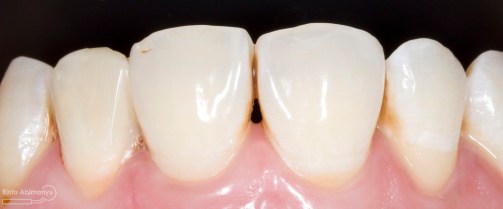

Pada pemeriksaan intra oral terlihat gigi 23 dan 24 mengalami karies dan cukup banyak sisa makanan terjebak disana…

Pemeriksaan respon dingin pun menunjukkan hasil negatif, untuk menambah data dalam penegakan diagnosis maka dilakukan pengambilan ronsen pada gigi2 tersebut